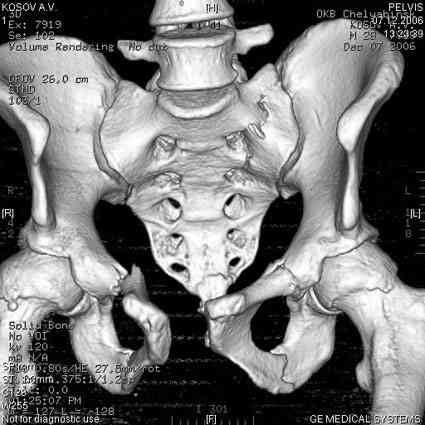

Уважаемые коллеги! опять вопрос по повреждению таза. Больной получил производственную травму 10 дней назад - удар балкой около 3 тонн в область верхней трети правого бедра и лона.

Был диагностирован перелом "типа бабочки" и повреждение уретры. Сделана цистостома. У насв отделении 3 дня. Имеется огромная флюктуирующая гематома с "галифе"-образной деформацией обеих бедер. Пнкционно эвакуировали в несколько приемов из подфасциальных полостей на бедрах около 3 литров геморрагического отделяемого с последующей эластической компрессией. При пункциях выявлено сообщение полостей на бедрах - видимо через поравннуюдиафрагму дна и полость таза - при удалении крови справа уменьшался объем левого бедра. Какой то активности проявялять покабоимся - аппаратная фиксация через отслоенные ткани представляется чреватой нагноением, открытая фиксация в условиях такой гематомы тоже не радует. Хотелось бы услышать ваше мнение

18.12. - отдельное спасибо еще раз А.В.Рункову- больного оперировали (А.В.Рунков) - произведен остеосинтез аппаратом - фиксация за крылья, два стержня в лонные кости и репозиция (почти полная) снимки будут чуть позже.